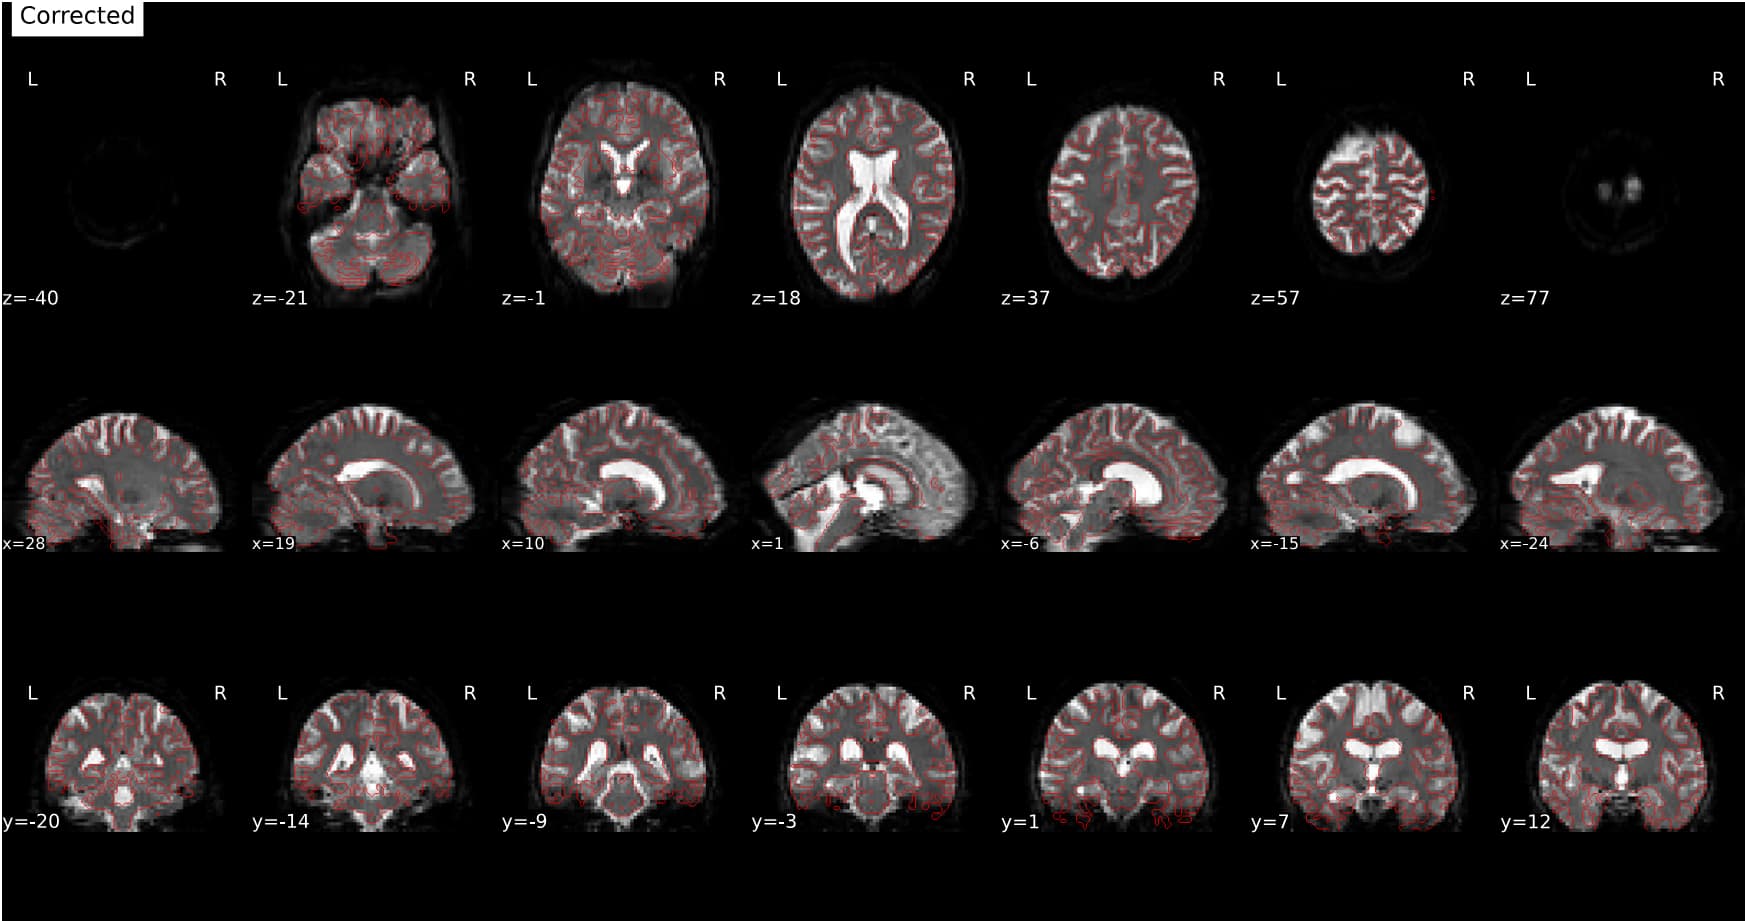

feed FMRIPREP with the undistorded, motion corrected

BOLD_u.nii.gz(4D timeserie corrected by SynBOLD-DISCO) and tell fmriprep to not run SDC (susceptibility distortion correction) on this data. That would work, but with the disadvantage of interpolating twice (= more smoothing) the data (once with SynBOLD-DISCO and once with fmriprep). Also motion correction will be done twice in that case: once with SynBOLD-DISCO and once with FMRIPREP, so you could not use the motion parameters calculated by fmriprep but instead need to use the motion parameters from Syn-BOLD-DISCO for your GLM and motion outliers. Or you could try to not run motion correction with SynB0-DISCO but I guess that would affect the accuracy of SDC with SynB0-DISCO. -